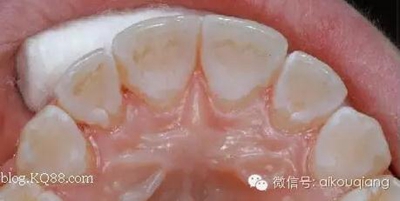

其實(shí)還有一種我們也經(jīng)常采用的固定保持器,效果不錯,除了黏結(jié)有點(diǎn)麻煩外,其實(shí)也是不錯的選擇!